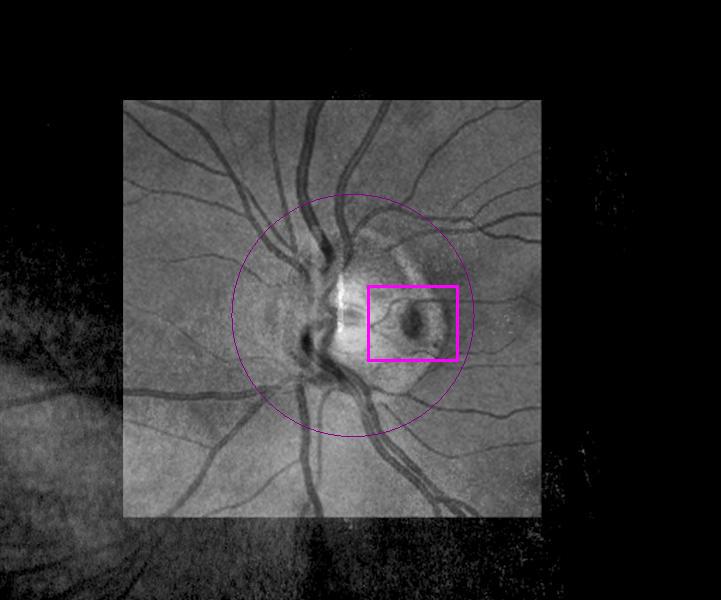

Grubenpapille (siehe Anmerkung)

Papillengrube (аббревиатура: Grube)